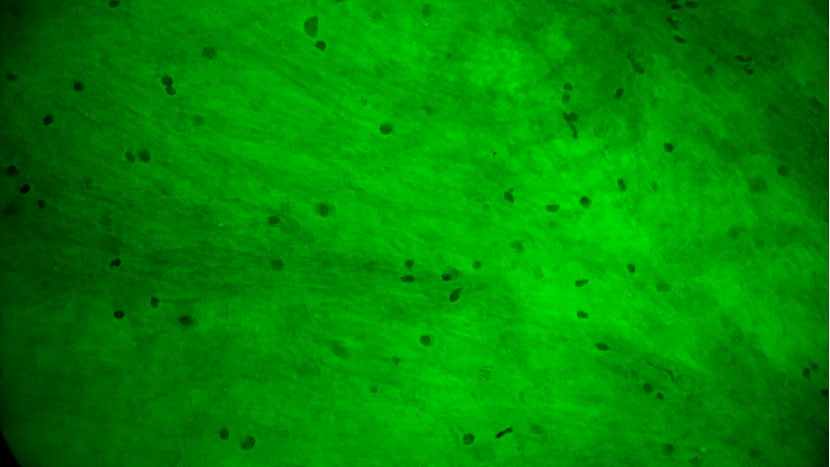

术中EndoSCell®细胞图像如下:

手术切缘处发现的正常脑白质:细胞核形态正常,密度低且分布均匀